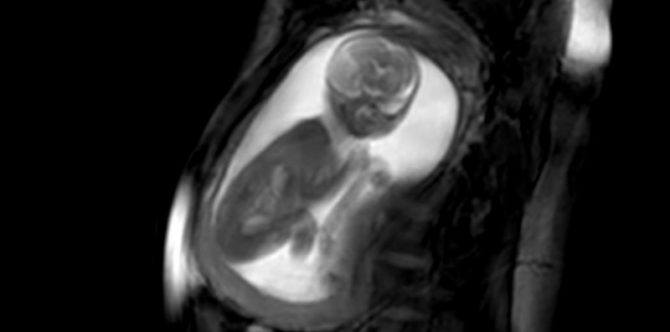

The anatomy ultrasound is not only valuable for health professionals, but also allows moms and dads to clearly see their unborn child.

One of the most exciting moments as an expecting mom or dad is to see your unborn child’s first few movements inside the womb. But these are usually very grainy images, plus you need the help of a doctor to get a good look at your child.

But through the help of new technology called anatomy ultrasound, you will now be able to clearly see your child moving inside the womb!

The anatomy ultrasound was developed by researchers and clinicians at the iFind project. The project aims to “allow screening of foetal abnormalities in an automated and uniform fashion.”

Researchers developed it using techniques in ultrasound, MRI, robotics, and computing. This combination of technologies makes it possible to capture the most amazing images and videos. These images are the clearest so far.

Another important point is that this type of ultrasound is safe to use in pregnancies, potentially making it a better option for moms in the future.

Looking at the videos, the images are pretty clear and spectacular!